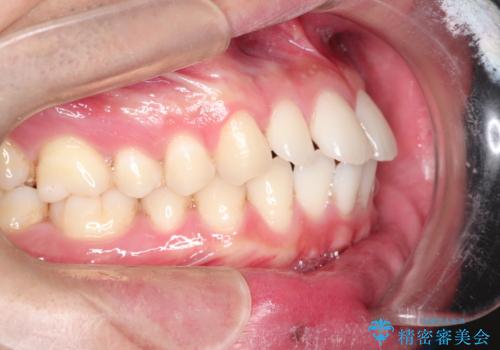

前歯の隙間を閉じたい 口元も下げたい ハーフリンガルによる抜歯矯正

- 上の前歯の隙間と口元を下げたとのことで来院されました。

上顎正中離開と、口唇の突出感がありました。

上下左右の歯を1本ずつ抜歯しして、上顎の前歯を後方に移動させるのと、正中の隙間を閉じる計画としました。

装置はなるべく目立たないものをご希望でしたので、ハーフリンガルを選択されました。